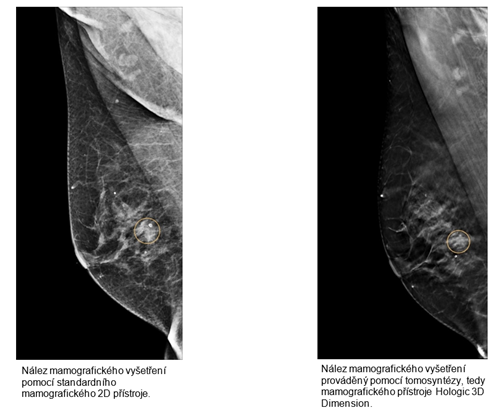

„Základní rozdíl mezi standardní mamografií a tomografií je, že tomografický přístroj je schopen pořídit více snímků v tenčích vrstvách. Ty jsou pak v počítači zkompletovány do třírozměrného zobrazení a výsledný obraz vykreslí vnitřní struktury prsu. Pokud se objeví jakákoliv nejasnost, můžeme se podívat na podezřelé místo znovu a zkontrolovat ložisko vrstvu po vrstvě,“ vysvětluje MUDr. Halka Bitmanová, vedoucí lékařka mamocentra EUC Kliniky České Budějovice.

Rameno přístroje Hologic 3D Dimension se pohybuje nad upevněným prsem a pořizuje 11–15 snímků z různých úhlů a rovin. Software následně dokáže mléčnou žlázu zrekonstruovat a vyobrazit ložiska podle toho, v jaké vrstvě jsou uložena. Detailní zobrazení dokáže upřesnit i rozsah například drobných kalcifikací a jejich rozložení ve vrstvách žlázy. „Metoda tomografie je vhodná především při screeningu pacientek s hutnou mléčnou žlázou. Lze totiž odhalit změny, které se při běžné mamografii do struktury žlázy ‚schovají‘. Na klinice v Českých Budějovicích technologii využíváme až po provedení klasického mamografického vyšetření, k detailnějšímu rozboru nejasných nálezů,“ upřesňuje MUDr. Halka Bitmanová, a dodává, že tomosyntéza by mohla do budoucna pomoci i při mamografických vyšetřeních u mladších žen. „V blízké budoucnosti počítáme s tím, že budeme provádět tento typ mamografického vyšetření z důvodu podezřelého nálezu v prsu i u mladších žen, které zatím nespadají do věku pro screening, ale i u těch, které mají prsní žlázu hutnou, a tedy hůře přehlednou. Celý proces se díky tomu výrazně zpřesní,“ doplňuje MUDr. Bitmanová.